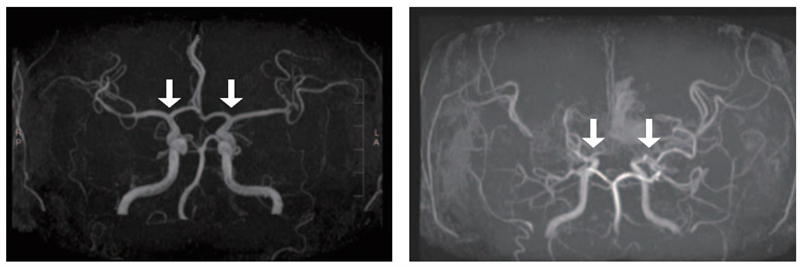

▲(왼쪽부터) 정상 및 모야모야병 환자의 뇌혈관

소아 모야모야병은 뇌로 혈액을 공급하는 혈관이 특별한 원인 없이 점차 좁아지는 만성 진행성 뇌혈관질환이다. 이 질환이 있으면 부족한 혈류를 보충하기 위해 비정상적인 미세혈관이 형성되는데, 이들은 혈류를 충분히 공급하기 어렵고 파열되기 쉬워 뇌경색·뇌출혈 등 소아 뇌졸중을 유발할 수 있다.